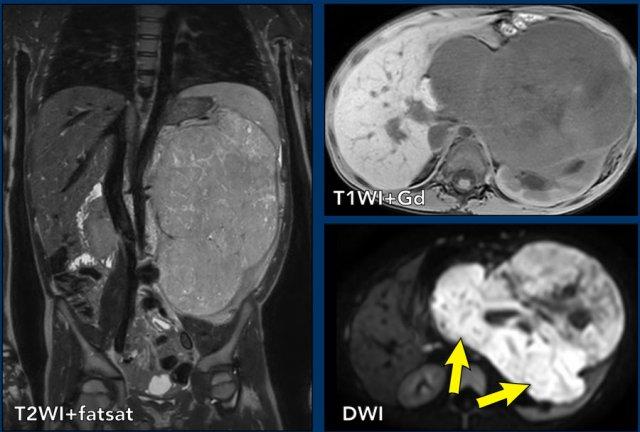

Ca lâm sàng 1

Hình ảnh chuỗi xung T2W mặt phẳng coronal cho thấy một khối u không đồng nhất ở thận trái với các thành phần nang nhỏ.

Khối u ngấm thuốc kém hơn so với phần nhu mô thận bình thường còn lại ở ngoại vi.

Các thành phần đặc của khối u cho thấy hạn chế khuếch tán rõ rệt (mũi tên).

Đây là u Wilms ở bé trai năm tuổi. Hóa trị tiền phẫu được thực hiện theo phác đồ Umbrella của SIOP-RTSG, sau đó tiến hành cắt thận.